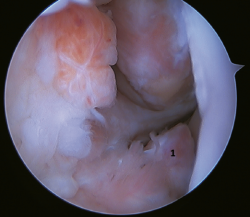

La principal indicación de esta reparación es la rotura del fascículo superior del LTFA de su inserción fibular, presentando una buena calidad tisular del remanente de ligamento (Figura 3).

Figura 3. A: identificación de la inserción fibular del LTFA (*) con excelente calidad del remanente tisular; B: técnica con dos implantes sin nudos y a través de un portal anterolateral único modificado; C: resultado final. P: peroné; T1: túnel talofibular; T2: túnel calcaneofibular.